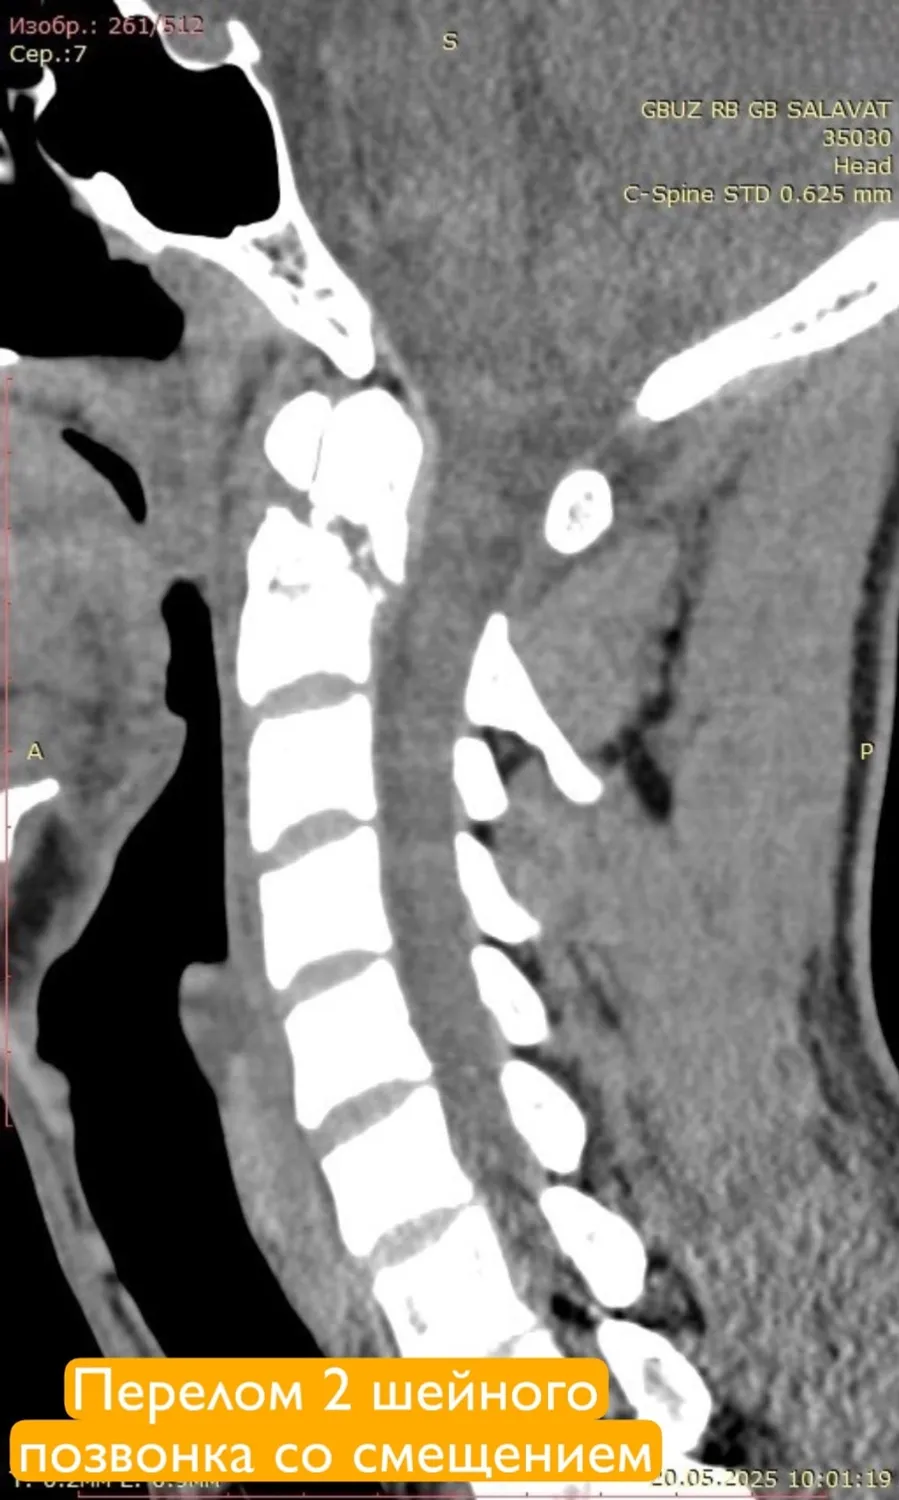

У пациента диагностировали сочетанную травму: ушиб головного мозга, переломы шейных и грудных позвонков, а также ребер и ушиб легких. Особенно серьезной была ситуация с переломами 1 и 2 шейных позвонков со смещением. Травма могла привести к острому сдавлению спинного мозга и угрожать жизни молодого человека. Такие переломы часто приводят к инвалидизации, вплоть до полного обездвиживания.